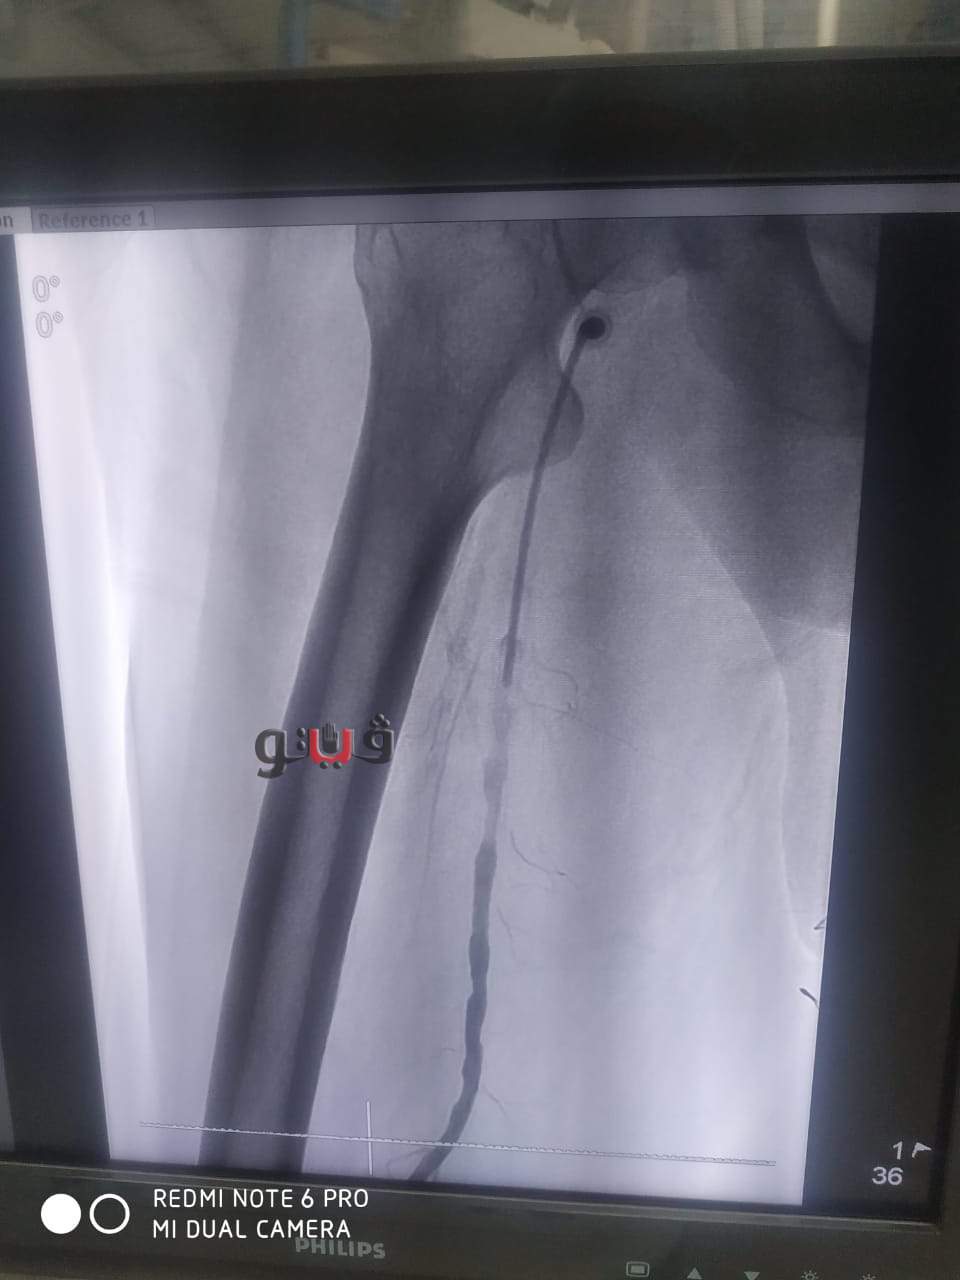

نجاح عملية توسيع بالوني بالقسطرة الطرفية لمريض بمستشفى المنصورة الدولي

شهد مستشفي المنصورة الدولي بمخافظة الدقهلية نجاح فريق طبي بإجراء عملية توسيع بالوني لمريض يبلغ من العمر 65عاما يعاني من قصور دموي حرج بالساق اليمنى.

وأوضح مكي انه تم التدخل الطبي السريع عن طريق القسطرة الطرفية داخل وحدة القسطرة التداخلية بمستشفى المنصورة العام الجديد (الدولي) وتم استعادة وتقوية الدورة الدموية للساق بنجاح عن طريق فريق طبي من قسم جراحة الاوعية الدموية بالمستشفى حيث تمت العملية بنجاح باهر وخرج المريض من العمليات بحالة مستقرة.